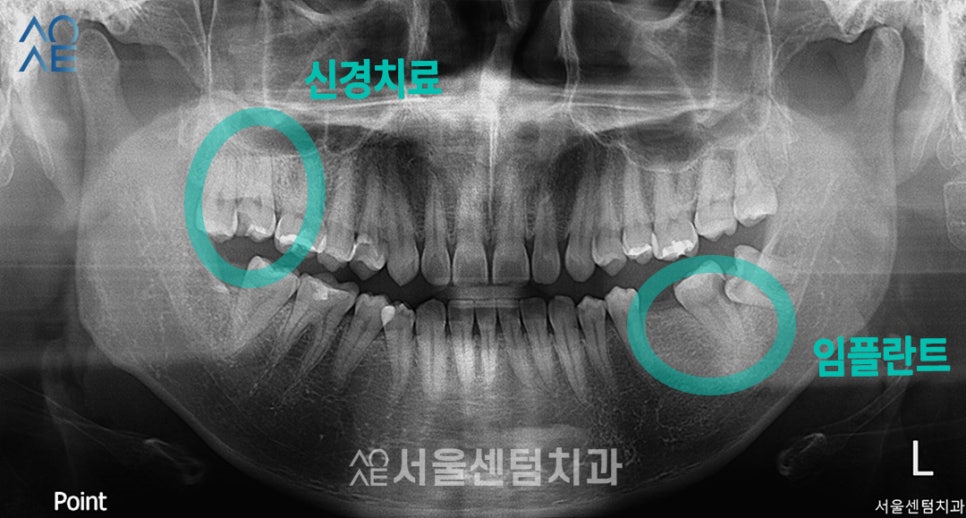

치료가 필요한 치아의 부분에

표시를 해두었습니다.

(사진과 실제 치아는 반대 방향입니다)

| 🦷현재 상태 &치료 계획🦷 |

| (1) 현재 상태🔹 사랑니로 인해 손상된 어금니 있음🔹치아의 절반 이상 충치가 진행된 치아 있음 |

| (2) 치료 계획🔹[오른쪽 위] 어금니 신경치료🔹[왼쪽 아래] 사랑니발치🔹[왼쪽 아래] 임플란트 2개 식립 |